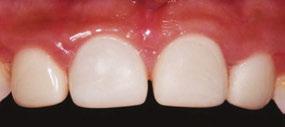

Several clinical solutions exist for primary anterior teeth with multisurface decay. Full coronal restoration of carious primary incisors may be indicated when caries is present on multiple surfaces, pulpal therapy is indicated, caries may be minor, but oral hygiene is very poor, or in a child with severe early childhood caries or a high caries risk diagnosis.1 Depending on the clinical scenario, a minimally invasive approach with the utilization of a high viscosity glass ionomer cement (HVGIC), with or without the combination of silver diamine fluoride (SDF) in a strip crown form, may pause the caries progression and provide an adequate clinical solution. Resin composite strip crowns have shown 80% retention rates and adequate parental satisfaction,1-4 although composite resin strip crowns have shown lower retention rates in teeth with decay involving three or more surfaces and particularly in children with a high caries risk4-6 (Figure 1). This could be from the continued high caries risk behaviors of the patient, as composite resin strip crowns in this population have shown to have increased inflamed marginal gingiva and gingival bleeding, increased plaque retention along the restoration, and loss of some restorative material.5,6

Alternatively, a resin-faced stainless steel crown provides a full coverage restoration with excellent retention.7 These crowns can serve as a full-coverage restoration with or without the resin facing, but the loss of resin facing can be a major esthetic concern for parents.7 Preformed pediatric zirconia crowns address many of the undesirable clinical outcomes of other restorative materials. Their biocompatibility, demonstration of excellent marginal gingival health, low plaque retention, high parental esthetic acceptance, and high survival probabilities make them an excellent clinical choice in the patient with severe early childhood caries.1,4,5,8-13

With parental interest increasing in esthetic treatment options for complex anterior caries, preformed pediatric zirconia crowns are becoming the treatment of choice for patients with a high caries risk or a severe early childhood caries diagnosis.14

This review discusses three clinical cases in which NuSmile® ZR (NuSmile, Houston, Texas) anterior pediatric zirconia crowns were the correct clinical decision in varying clinical scenarios.

around these clinical sites. His anterior zirconia crowns showed healthy gingival margins with little-to-no plaque accumulations. This positive clinical finding is from the highly polished nature and biocompatibility of pediatric zirconia crowns. These restoration features limit plaque accumulations on the restoration and along the marginal gingiva, providing a localized positive aspect directly related to the choice of restorative material (Figure 2).

A 3-year-old female presented with pulpal necrosis and abscess on #E and pulpal necrosis on #F. Extraction therapy or pulpectomy was offered. The family was highly motivated to retain #E and #F. The pulpectomy was performed with 0.02 K-Flex hand files, 3% NaOCl with a lateral vented needle, obturated with Vitapex (Neo Dental International Inc., Federal Way, Washington), a premixed paste of calcium hydroxide and iodoform. The access was filled with a HVGIC sealing the pulp therapy and increasing the clinical success by minimizing the potential for bacterial contamination. NuSmile ZR anterior crowns were selected as offering a full-coverage, esthetic, cemented restoration with no polymerization shrinkage when compared to a composite restoration. Crowns were cemented with NuSmile® BioCem (NuSmile, Houston, Texas). This is clinically beneficial as the provider would want to cement a restoration that provides limited microleakage minimizing the potential for bacterial contamination.15-17 At 6-month follow up, lesion healing had occurred with healthy gingival margins and no plaque accumulations (Figure 3).

had been previously treated using SDF and covered with a HVGIC in a strip crown form. Though her lesions were stable from the clinical success of the SDF and HVGIC, these restorations were starting to fracture and demonstrate loss of material. The family wanted a more esthetic treatment option that would have a longer survivability. Additionally due to her high caries risk nature, a full coverage restoration with NuSmile® ZR anterior crowns were a more ideal solution in stabilizing her extensive decay pattern and covering staining from SDF therapy (Figure 4).

Figure 3: NuSmile® ZR Crowns were selected as a cementable full coverage restoration. At 6-month recall, apical tissues were healed with excellent gingival health Figure 4: SMART style restorations that were definitively restored with NuSmile® ZR Crowns as an esthetic option to cover SDF staining